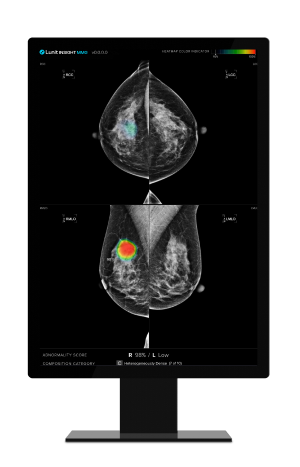

▲ Lunit's AI-powered mammography analysis solution 'Lunit INSIGHT MMG'